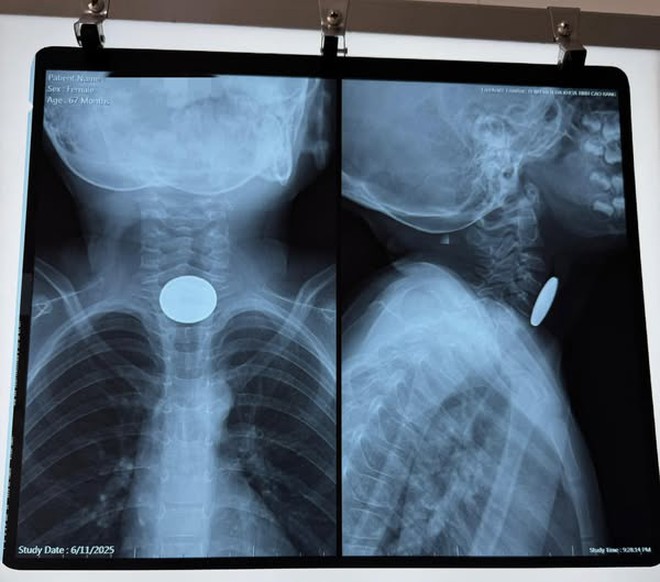

Ngày 11/6, BVĐK tỉnh Cao Bằng tiếp nhận một trường hợp cấp cứu do nuốt dị vật. Bệnh nhi là bé gái 67 tháng tuổi, trú tại TP Cao Bằng, được đưa vào viện trong tình trạng khó nuốt, buồn nôn nhưng không nôn được, có biểu hiện khó thở sau khi chơi một mình tại nhà.

Sau thăm khám và hội chẩn khẩn, các bác sĩ xác định có dị vật đường tiêu hóa trên, nghi mắc ở thực quản. Ê kip gây mê và bác sĩ đã nhanh chóng tiến hành nội soi thực quản ống cứng cấp cứu.

Dị vật được lấy ra là đồng xu kim loại màu trắng, đường kính khoảng 2,5cm, mắc cách cung răng trên khoảng 12cm. Bé tiếp tục được theo dõi tại khoa Tai Mũi Họng - BVĐK tỉnh Cao Bằng sau thủ thuật.

Bác sĩ Nông Hoàng Mạnh, người trực tiếp xử lý ca cấp cứu trên cho biết, nếu không kịp thời can thiệp, dị vật kim loại lớn có thể gây tắc thực quản, tổn thương niêm mạc hoặc đe dọa tính mạng nếu rơi vào đường thở.

Hình ảnh đồng xu khi mắc ở thực quản của bé gái và sau khi được gắp ra. Ảnh: BVCC.